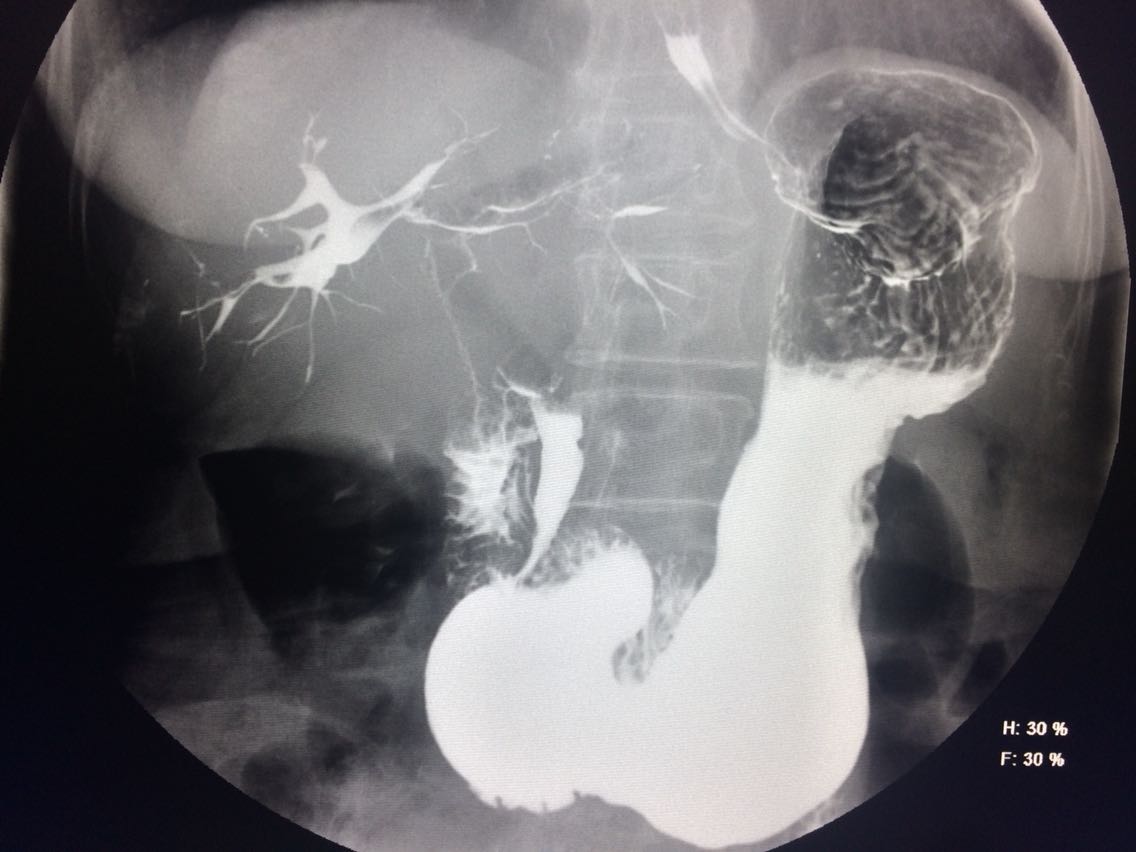

查体未见明显异常。 上消化道造影如图。

诊断食管癌。 造影剂逆流入胆道。